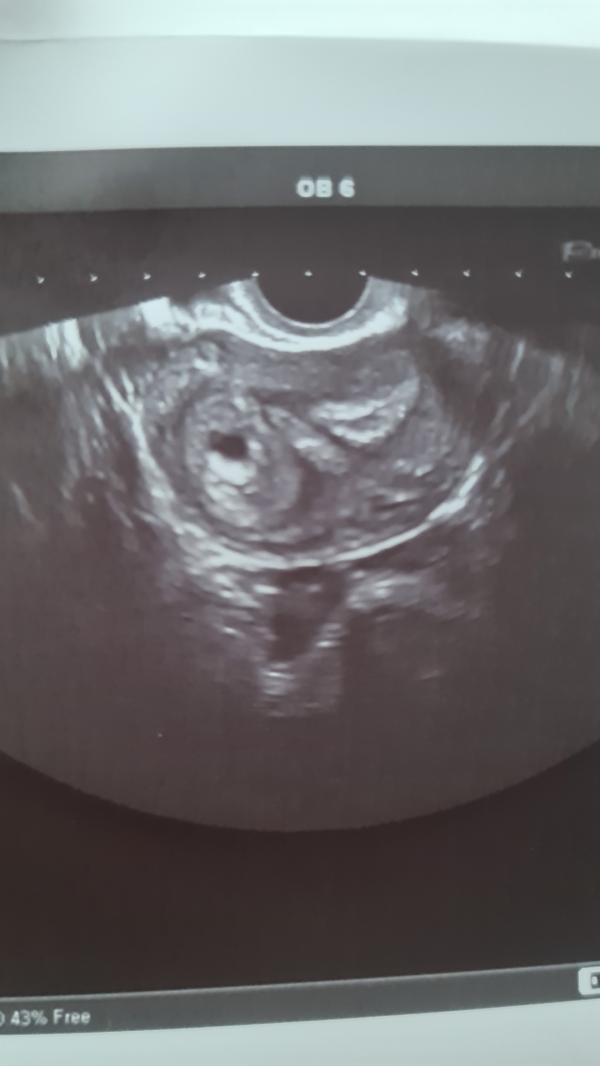

Я ложусь,он вставляет датчик с абсолютно спокойным настроем и тут он такой😱😱😱"Анастасия, вы что в себя поверили?вы как-то жёстко занимались сексом?африканские страсти?" И смеется сквозь шок и удивление во взгляде) мы начинаем ржать,я отшучиваюсь тоже,тут он зовет коллегу и медсестру и показывает картинку и говорит:"Вы знаете,то что я вижу не имеет ни медицинского,ни физиологического объяснения!я не знаю как это получилось,это можно считать чудом..или волшебством..". Ну и разворачивает экран ко мне и показывает, как матка разделилась ровно на 2 половины и в одной есть плодное яйцо,там эмбриончик и бьется сердечко(это уже видно,но не слышно),а с другой стороны грубейшие спайки и неоднородный эндометрий.В итоге он разрешил записать микро видео,где видно как качает сердечко и скзаал:"я сам тоже запишу видео,отправлю всем в институте,это просто капец ,я слов подобрать не могу и сейчас побегу к профессорам". Скзаал,чтоб я пришла через неделю еще раз,чтоб посмотреть как там развивается всё. ПО месячным было вчера 6.1 недель,а по плодному яйцу 5.5 недель,я думала что будет больше отставание,но нет,я рада))2 декабря увидимся снова.. и вот я опять переживаю,что же дальше будет с моей крошкой(((не помешает ли это всё развитию...слева плодное яйцо,а справа это все спайки,все эти неровности